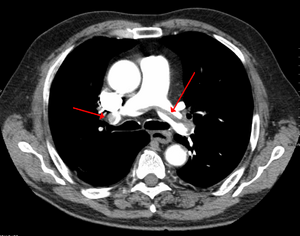

| Chest spiral CT scan with radiocontrast agent showing multiple filling defects both at the bifurcation ("saddle" pulmonary embolism) and in the pulmonary arteries. | |

On CT scan, pulmonary emboli can be classified according to level along the arterial tree.

Segmental and subsegmental pulmonary emboli on both sides

CT pulmonary angiography showing a "saddle embolus" at the bifurcation of the main pulmonary artery and thrombus burden in the lobar arteries on both sides.

التصوير الطبقي المحوسب

التصوير الطبقي المحوسب للرئة والمصحوب باستخدام الصبغة المشعة في الوريد أصبح واسع الانتشار والاستخدام في تشخيص المرضى المشتبه بإصابتهم بالانصمام الرئوي، لهذا النوع من التصوير حساسية تبلغ 83% ودقة نوعية تصل إلى 96%.[24].[25]